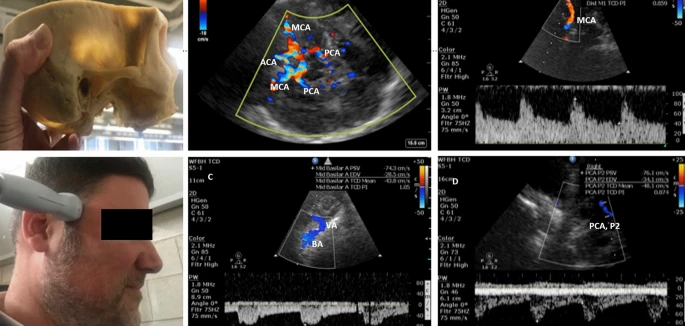

#ONSD #TCD #TTE #LUS #IVC #SoME #POCUS

bit.ly/3swctAh

@PennUltrasound @WCMCNeurology @MountSinaiNCC @ColumbiaNCC @YaleNeuroICU @AlexReynoldsMD @ghoshal_shivani @drdangayach @atulkalanuria @oneDRwoman_ @rkchoi @aartisarwal @judyhtchang @mel_para @rlcschuler

University of Pennsylvania Neurology@PennNeurology

Looking further than a pocket of fluid. How do you use POCUS in your practice? @PennUltrasound @PennMedicine @PennMDForum @PennHospitalist @PennIMResidents @ImPennsy @PennNSG @PennAnesthesia @Penn_ENT @PennRadiology @PennGIHep @pennsurgery @PennVascular bit.ly/3ek6WVp